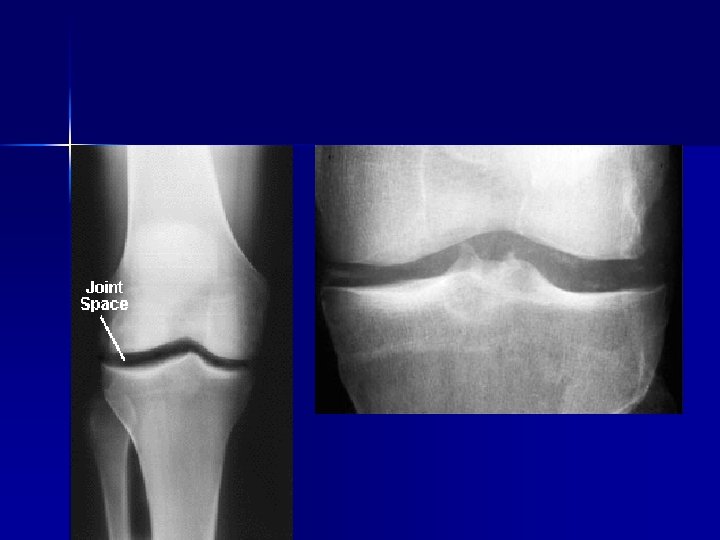

Artrose Kraakbeendegeneratie n Osteofyten n Gewrichtsspleetvernauwing n geoden n

artrose

Artrose van de knie Pijn n Verminderde beweeglijkheid n Zwelling n Mobiliteitsverlies n levenskwaliteit n